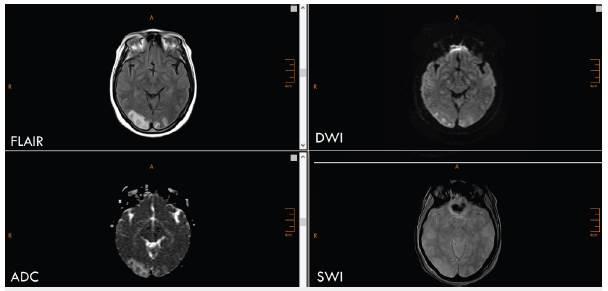

El edema citotóxico en IRM brilla o es hiperintenso en las secuencias de difusión (DWI) y es oscuro o hipointenso en los mapas de coeficiente de difusión aparente (ADC). El vasogénico es hipo o ligeramente hiperintenso en las imágenes en DWI, pero brilla en los mapas ADC 10 (figuras 1 y 2).

Fuente autor.

Figura 1 Paciente con ACV isquémico agudo de la arteria cerebral media derecha. Se observa hiperintensidad en las secuencias de DWI (flecha blanca), hipointensidad en los mapas ADC (flecha blanca), sin alteraciones en FLAIR ni evidencia de sangrado en las imágenes de susceptibilidad (SWI). Se observa además infarto antiguo hemodinámico (flecha amarilla).

En las IRM se observa edema citotóxico en la fase aguda con hiperintensidad en la DWI, hipointensidad correspondiente en los mapas ADC e hiperintensidad en ELAIR a partir de aproximadamente 4,5 horas 18 (figura 1).